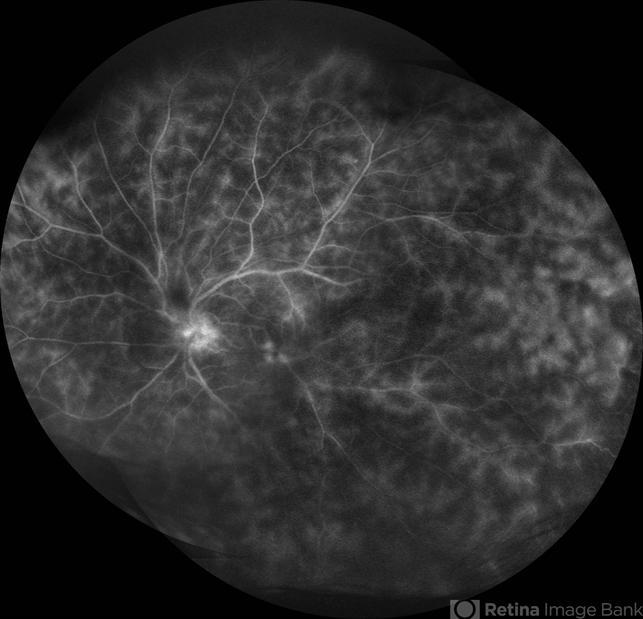

- vasculitis, diffuse vasculitis

- A 27-year-old male patient presented with vasculitis in left eye. Fluorescein angiography image showed diffuse vascular leakages.